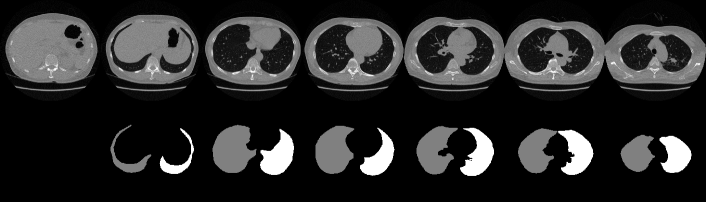

We used a publicly available pretrained lung segmentation network, U-net-R231 [29], to segment lung regions from each 3D stack of CT slices. We used the COVID-19 dataset [36] to evaluate the lung segmentation performance. The intersection of the ground truth for the 3D lung region with the U-net-R231 prediction was evaluated using the intersection over union (IoU) and Dice score and averaged across slices and stacks, obtaining the results listed in Table B. Compared with the performance evaluation results using the datasets in [29] (i.e., lung tissue research consortium––LTRC [37], lung CT segmentation challenge 2017––LCTSC [38], and vessel segmentation in the lung 2012––VESSEL12 [39]) also shown in Table B, U-net-R231 provides a high Dice score, thereby validating its excellent lung segmentation ability. Fig. F shows results of lung segmentation by U-net-R231 to illustrate its excellent performance.